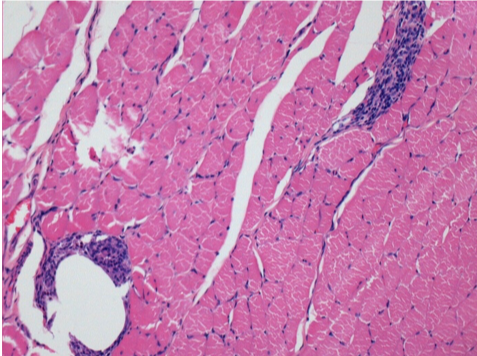

Iniezione Endopeel nel tessuto subcutaneo SC

Scatola 6

0.5 ml ( 5x 0.1ml): Iniezione SC di Endopeel nel tessuto pretibiale subcutaneo SC destro (Dx).

Sx:200x-Controllo-SC

Dx-Giorno10-SC-200X

Dx-Giorno30-SC-200X

Dx-Giorno90-SC-200X

Dx-Giorno210-SC-200X

Dx-Giorno210-SC-400X

Endopeel induce una miofibrolisi selettiva reversibile e una risposta infiammatoria approssimativamente nel periodo di 1 mese.

I cambiamenti dei tessuti muscolari sono quasi completamente reversibili.

Il muscolo é il posto migliore per iniettare Endopeel ,per la sua maggiore efficacità, il controllo e la durata della sua azione.

Nessuna necrosi ne ascesso sono stati osservati durante la sperimentazione.